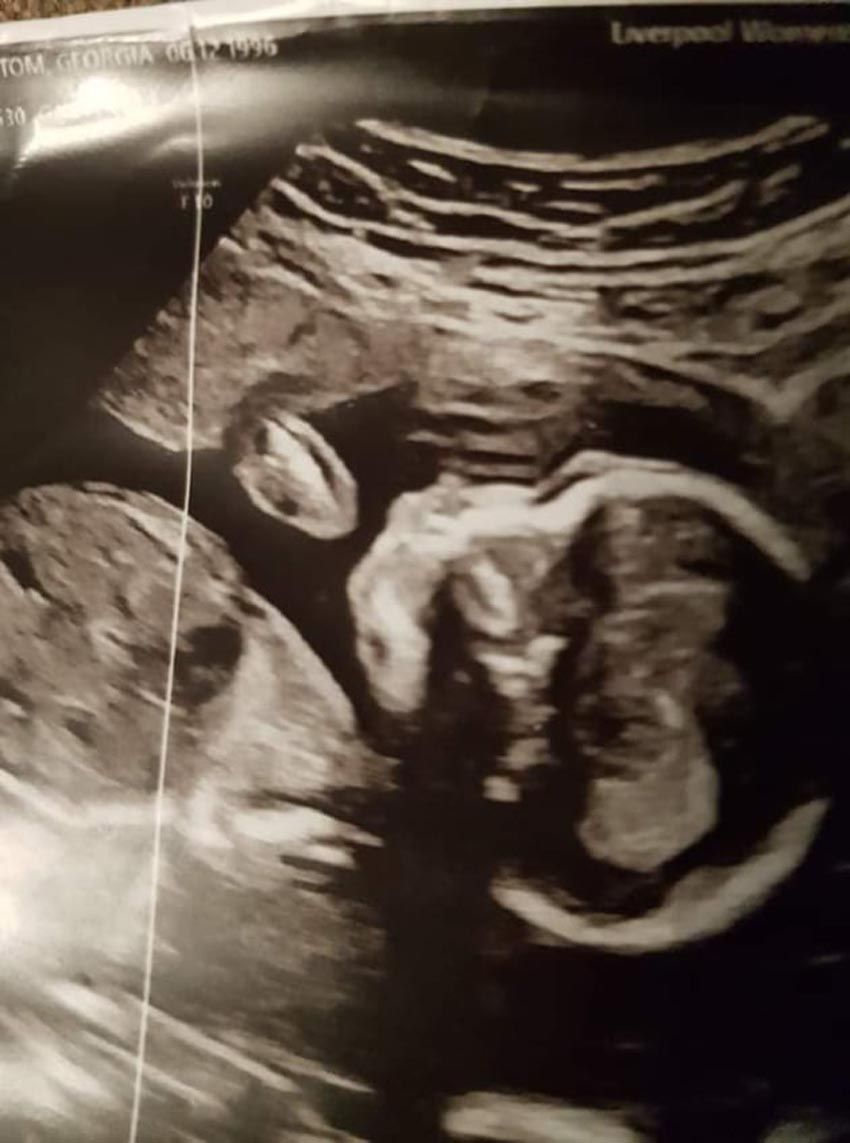

“They didn't tell me about the heart problems at that stage, as I don't think they were sure what was going on, but they referred me to Liverpool Women's Hospital where I had an appointment a few days later."

Georgia recalled: “I was really worried. I had two ultrasounds, then they sat us down and told us that she had a rare congenital heart defect called HPLS.